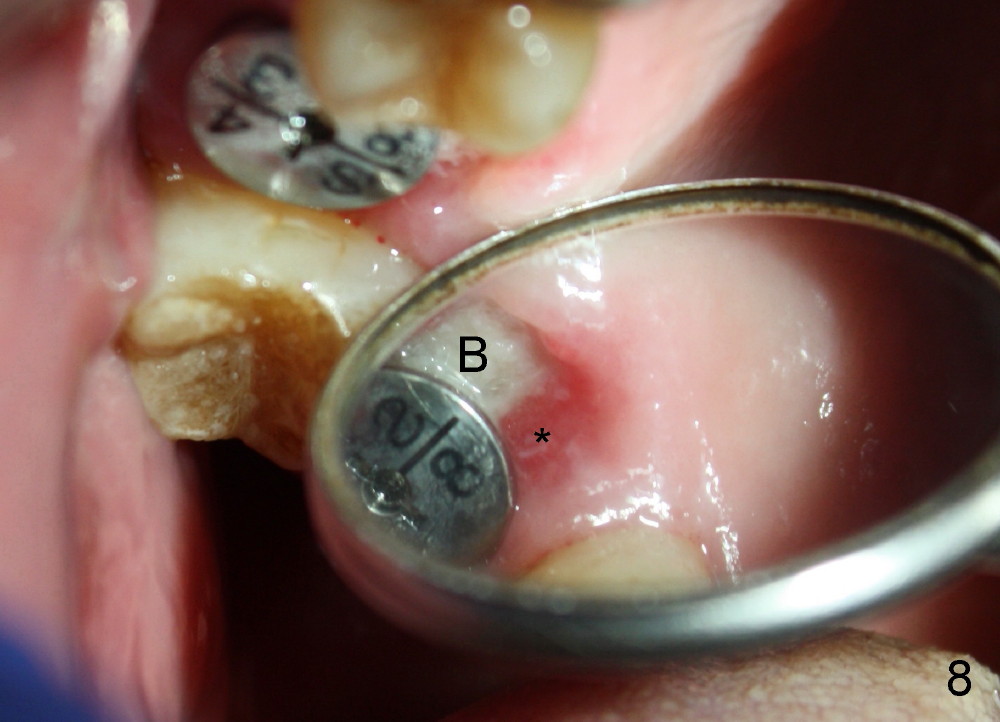

The tooth #3 has a crack line (Fig.1 ^). The septum (Fig.2 S) looks like an inverted pyramid (Fig.3), coronal part being pointed, whereas the apical broad. The shape of the septum is not so favorable to placement of tapered implant. Osteotomy starts with 1.5 mm pilot drill in the middle of the septum, followed by round tapered osteotomes 2 and 3 mm. The osteotomy begins to deviate into the mesiobuccal socket. The same osteotomes are used to re-direct the osteotomy palatally, followed by tapered drills, trying to move osteotomy palatally. A 4.5x17 mm tap is inserted with stability (Fig.4). Following using 5x17 mm tap at the depth of 12 mm, a 5.3x12 mm bone-level implant is placed ~ 1.5 mm below the crest, 1.5 mm above the septum (Fig.5). Demineralized cortical human allograft is placed in the remaining sockets and around the most coronal aspect of the implant (with a small piece of gauze placed in the implant well). After removal of the gauze, a piece of collagen membrane is pierced and carried by a 8.2x4/3 mm healing abutment and fixed in place (Fig.6 M). The periphery of the membrane is tucked underneath the gingiva. The wound is covered by perio dressing. The patient returns to clinic for follow up 8 days postop. There is no discomfort. In order to protect the collagen membrane (Fig.6), the perio dressing is intentionally not removed (Fig.7). Two weeks postop, the patient remains asymptomatic. After perio dressing removal, the membrane appears to have been resorbed (Fig.8 as compared to Fig.6). The bone graft (B), although exposed, remains in place and condensed, surrounded by healing healthy gingiva (*). The patient returns 2.5 months postop. The implant appears to osteointegrate (Fig.9, as compared to Fig.5). The buccal (Fig.10) and palatal (Fig.11) gingiva adapts to the healing abutment. When the healing abutment is removed for restoration 3 months postop, the gingiva looks healthy (Fig.12). A cemented abutment (5.8x4(2) mm) is placed; a crown is fabricated (Fig.13). The patient returns for recall 5 months post cementation. He reports food impaction distal to the crown. The gap mesial to the implant has closed (Fig.14).